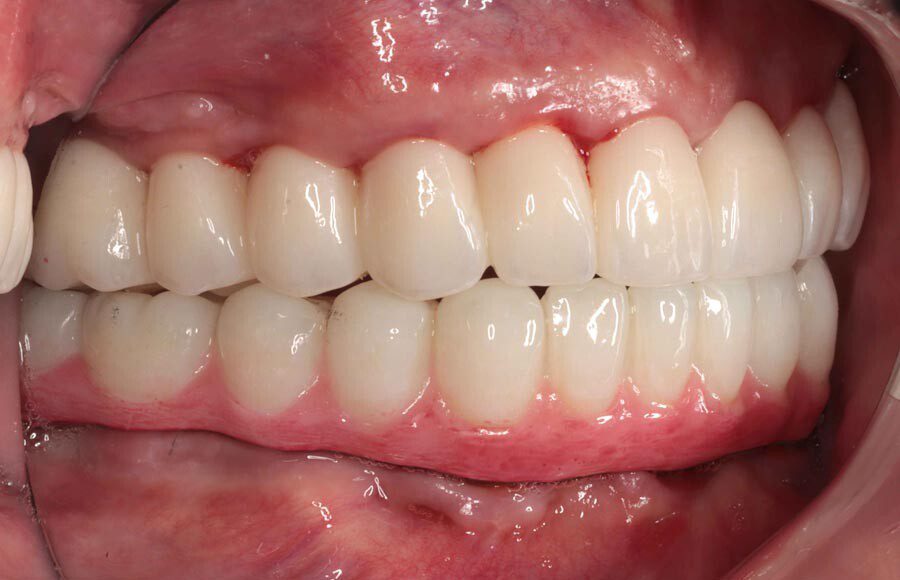

Final prostheses, intraoral, frontal. Homecare is still a problem. The final restorations are much kinder to the tissues and we hope this will resolve some of the inflammation.